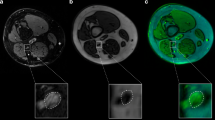

All participants underwent H-MRS examination at 1.5 T (Eclipse; Philips Medical Systems, Cleveland, OH, USA). Single-voxel spectra were obtained from an 8 ml cubic volume of interest placed within the right thalamus to encompass the VPL sub-nucleus (Fig. 1a). Two spectra were acquired: (1) long echo time (TE) (TE = 135 ms, resonance time [TR] = 1600 ms) using a point-resolved technique (Fig. 1b); and (2) short TE (TE = 20 ms, TR = 5000 ms) using a stimulated-echo acquisition mode technique with a mixing time of 12 ms (Fig. 1c).

a Axial section of the brain with voxel positioned to encompass the ventroposterior thalamic subnucleus. b Example spectra obtained at long TE using a point-resolved acquisition technique and c at short TE using a stimulated-echo acquisition mode acquisition technique with a mixing time of 12 ms. Cho Choline, Cr creatine, G + sI scyllo-inositol; Glx, glutamine/glutamate; lac, lactate; lip, lipids; mI, myo-inositol; NAA, N-acetyl aspartate